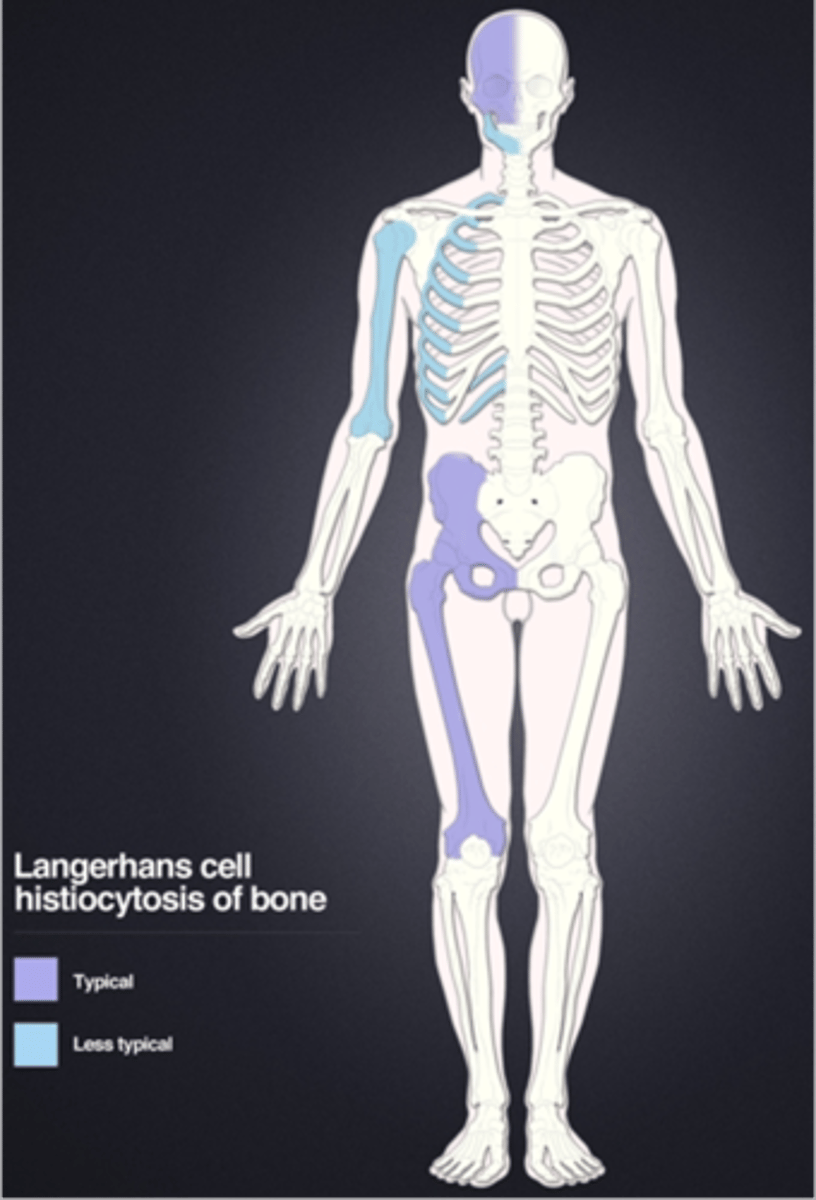

Langerhans Cell Histiocytosis

Eosinophilic granuloma is a type of _____

Eosinophilic granuloma

- <20 y.o. (peak 5-10 y.o.)

- Skull, mandible, pelvis, spine

- Monostotic > polyostotic

Beveled edge

ID radiographic feature of eosinophilic granuloma in the skull

Button sequestrum

ID radiographic feature of eosinophilic granuloma in the skull

Eosinophilic granuloma in the spine

ID benign tumor